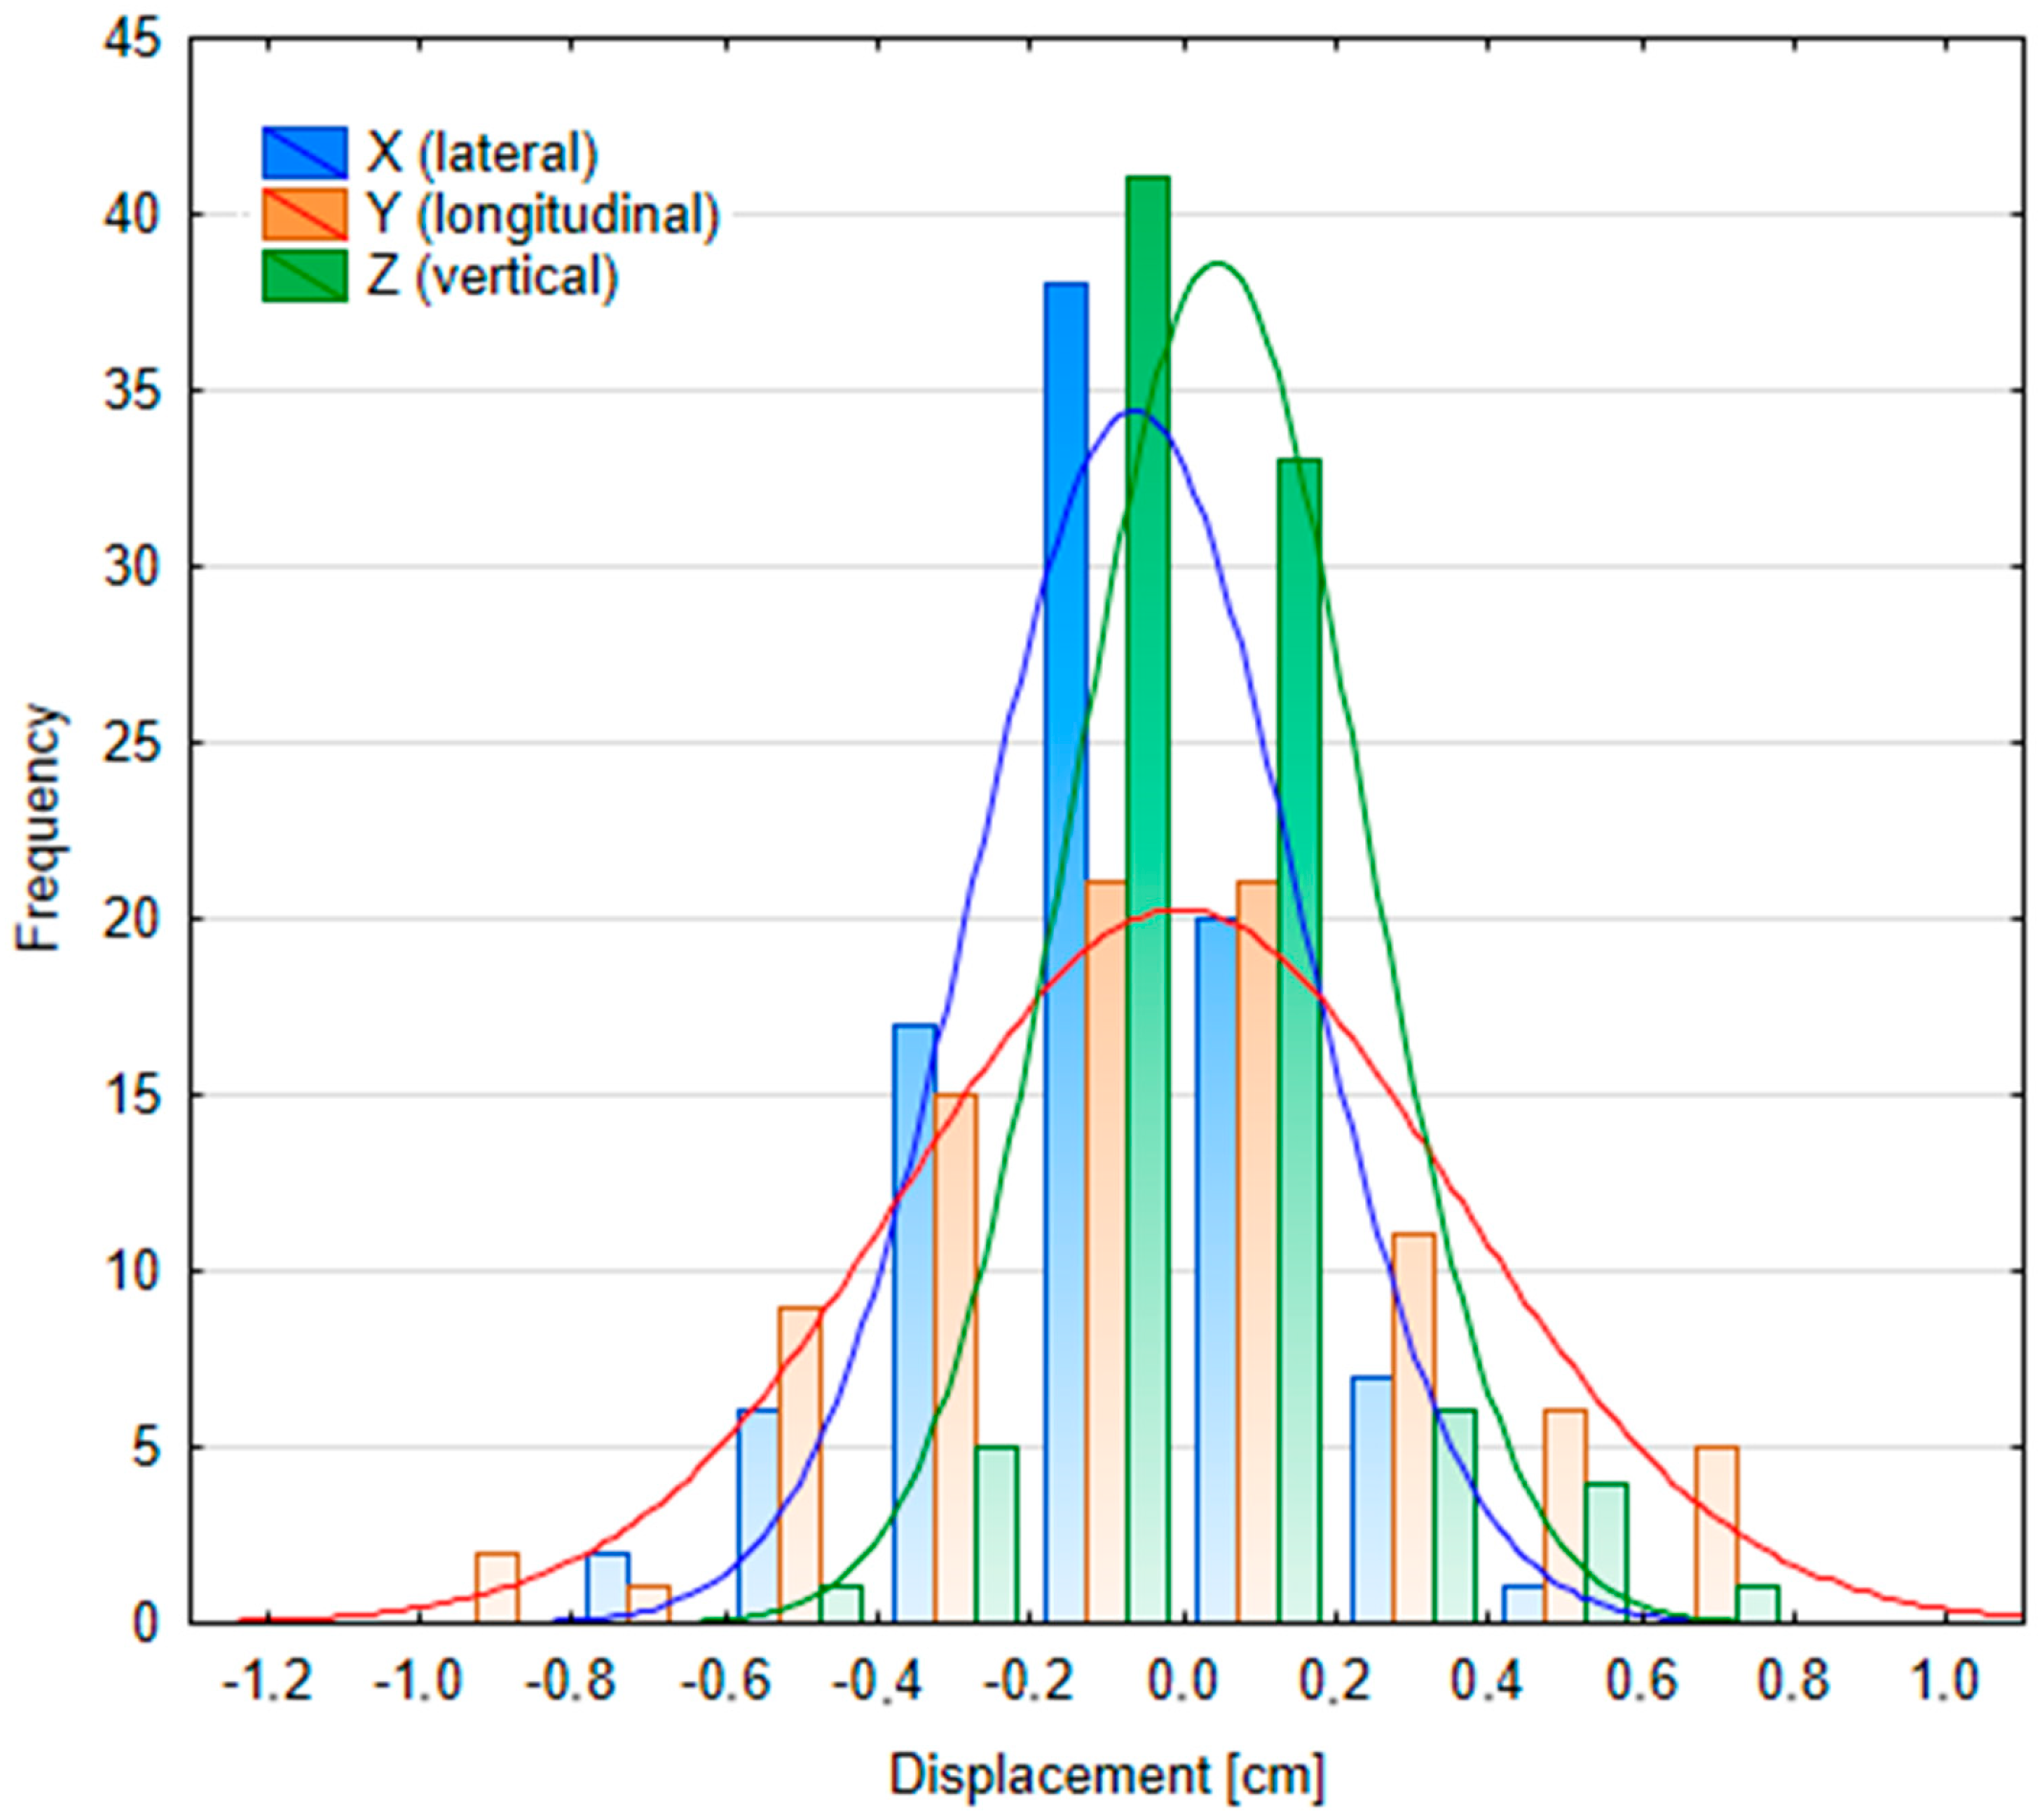

3.2.2. Patient Position Variability

| Table Shift Coordinates | Median SGRT FB Setup Error | Median SGRT DIBH Setup Error | Median SGRT DIBH Reproducibility Error | ||||||

|---|---|---|---|---|---|---|---|---|---|

| Male (n = 58) | Female (n = 46) | p-Value | Male (n = 49) | Female (n = 40) | p-Value | Male (n = 62) | Female (n = 69) | p-Value | |

| X (lateral) [cm] | 0.02 (−0.1; 0.04) | 0 (−0.06; 0.11) | p = 0.06 | −0.08 (−0.14; 0) | 0.08 (−0.03; 0.23) | p < 0.05 | 0 (−0.05; 0.03) | 0.03 (−0.01; 0.08) | p < 0.05 |

| Y (longitudinal) [cm] | 0.03 (−0,07; 0,13) | 0.08 (−0.07; 0.16) | p = 0.27 | −0.24 (−0.54; −0.02) | −0.25 (−0.43; −0.15) | p = 0.72 | 0.02 (−0.12; 0.13) | 0.11 (0.01; 0.19) | p < 0.05 |

| Z (vertical) [cm] | 0.08 (0.01; 0.13) | 0.12 (−0.06; 0.21) | p < 0.05 | −0.1 (−0.2; 0.06) | −0.16 (−0.27; −0.09) | p < 0.05 | 0.07 (−0.02; 0.13) | 0.02 (−0.01; 0.07) | p < 0.05 |

| MAG (magnitude) [cm] | 0.17 (0.14; 0.25) | 0.24 (0.15; 0.29) | p = 0.54 | 0.41 (0.22; 0.68) | 0.40 (0.23; 0.54) | p = 0.38 | 0.19 (0.13; 0.27) | 0.17 (0.12; 0.23) | p = 0.26 |

| ROT [°] | 0 (−0.44; 0.37) | 0.1 (−0.27; 0.53) | p = 0.24 | 0.23 (−0.02; 0.38) | −0.95 (−1.44; −0.12) | p < 0.05 | 0.22 (0.07; 0.35) | 0.03 (−0.19; 0.29) | p < 0.05 |

| PITCH [°] | 0.05 (−0.75; 1.17) | −0.97 (−1.72; −0.23) | p < 0.05 | 0.47 (−0.08; 1.21) | 0.06 (−1.14; 1.23) | p = 0.07 | −0.07 (−0.35; 0.3) | −0.28 (−0.61; 0.02) | p < 0.05 |

| ROLL [°] | 0.18 (−0.26; 0.69) | −0.13 (−0.70; 0.52) | p < 0.05 | −0.04 (−0.17; 0.17) | −0.21 (−0.77; 0.05) | p < 0.05 | 0.05 (−0.06; 0.16) | 0.19 (0.05; 0.28) | p < 0.05 |